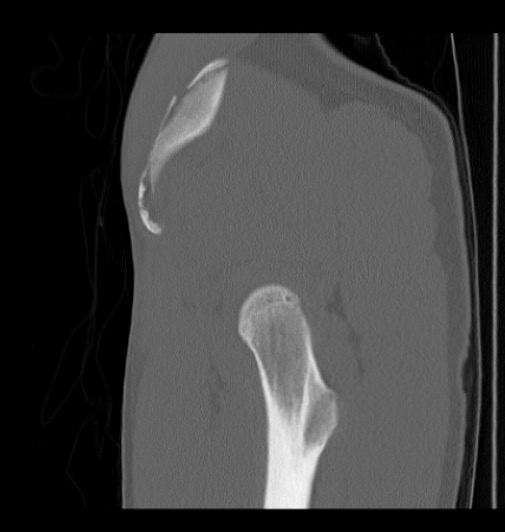

MRI

Ischial tuberosity avulsion 3Ischial tuberosity avulsion 2

Ischial tuberosity avulsion 1Ischial tuberosity avulsion 2

Ischial tuberosity avulsion